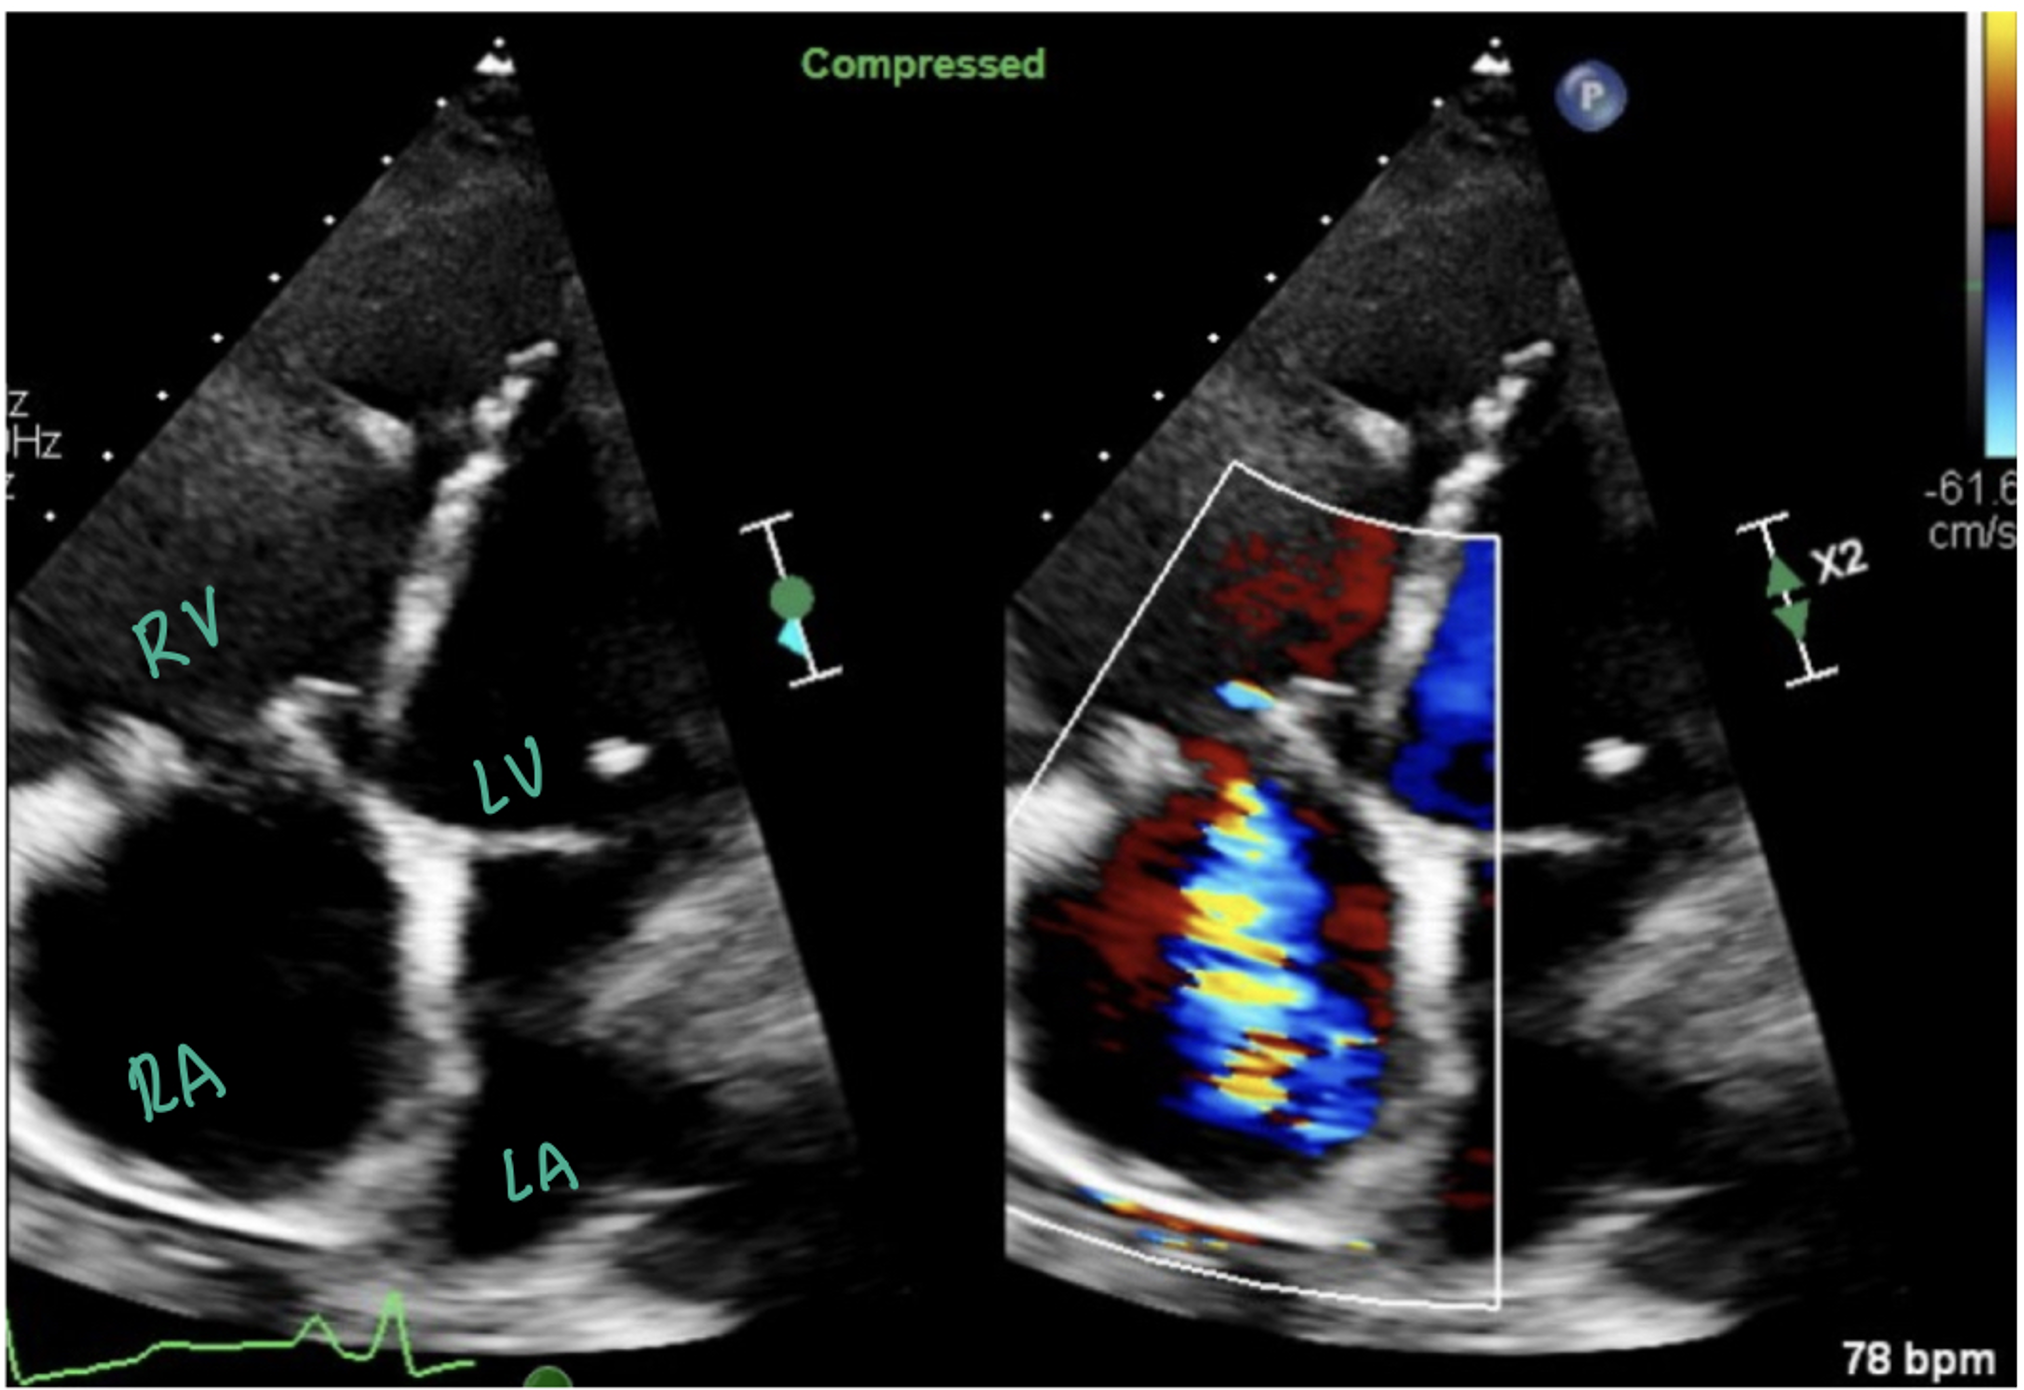

This image is a parasternal long axis depicting increased right ventricular (RV) pressure and size. Usually, the left ventricle (LV) should be greater than the RV. However, in this image, the RV is significantly enlarged which is consistent with increased right-sided pressures.

The picture above shows an apical four chamber view with color doppler over the right atrium (RA), showing a tricuspid regurgitation jet into the RA. The picture below shows continuous wave doppler through the tricuspid valve, which is a thick, well-defined curve signifying severe TR.